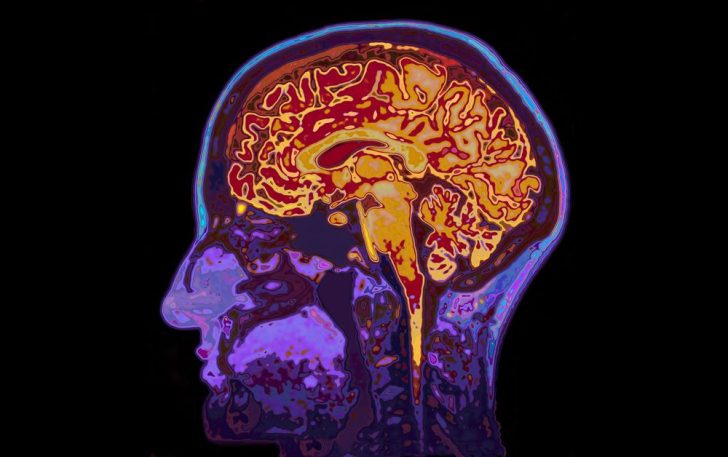

The neuroprotectant ApTOLL, a medication that may shield the brain from tissue damage, was linked to reduced death and disability among people being treated for stroke when used with standard treatments to restore blood flow, according to preliminary late-breaking science presented today at the American Stroke Association’s International Stroke Conference 2023. The meeting, held in person in Dallas and virtually Feb. 8-10, 2023, is a world premier meeting for researchers and clinicians dedicated to the science of stroke and brain health.

“The results are promising because for the first time a medicine studied as a neuroprotectant demonstrated not only a biological benefit by reducing the volume of damaged brain tissue, but also a reduction in long term disability and risk of death,” said study senior author Marc Ribó, M.D., an interventional neurologist at Hospital Vall d’Hebron in Barcelona, Spain.

In this clinical trial, researchers investigated if the neuroprotective medication ApTOLL may improve outcomes among people with stroke who also received standard treatment. ApTOLL is a TOLL-like receptor 4 (TLR4) antagonist involved in immune responses, yet it also responds to tissue damage. Previous studies in animals found that ApTOLL reduced inflammation and protected brain tissue from damage. Also, a first-in-human study in healthy adults did not find safety issues with ApTOLL.